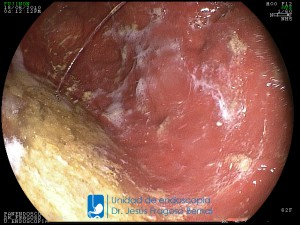

La Unidad de Endoscopía fue creada en 2002 por el Dr. Jesús Fragoso Bernal, es pionera en el estado por la utilización de la tecnología más avanzada, que nos permite ofrecer servicios integrales de diagnóstico y tratamiento para las enfermedades del aparato digestivo.